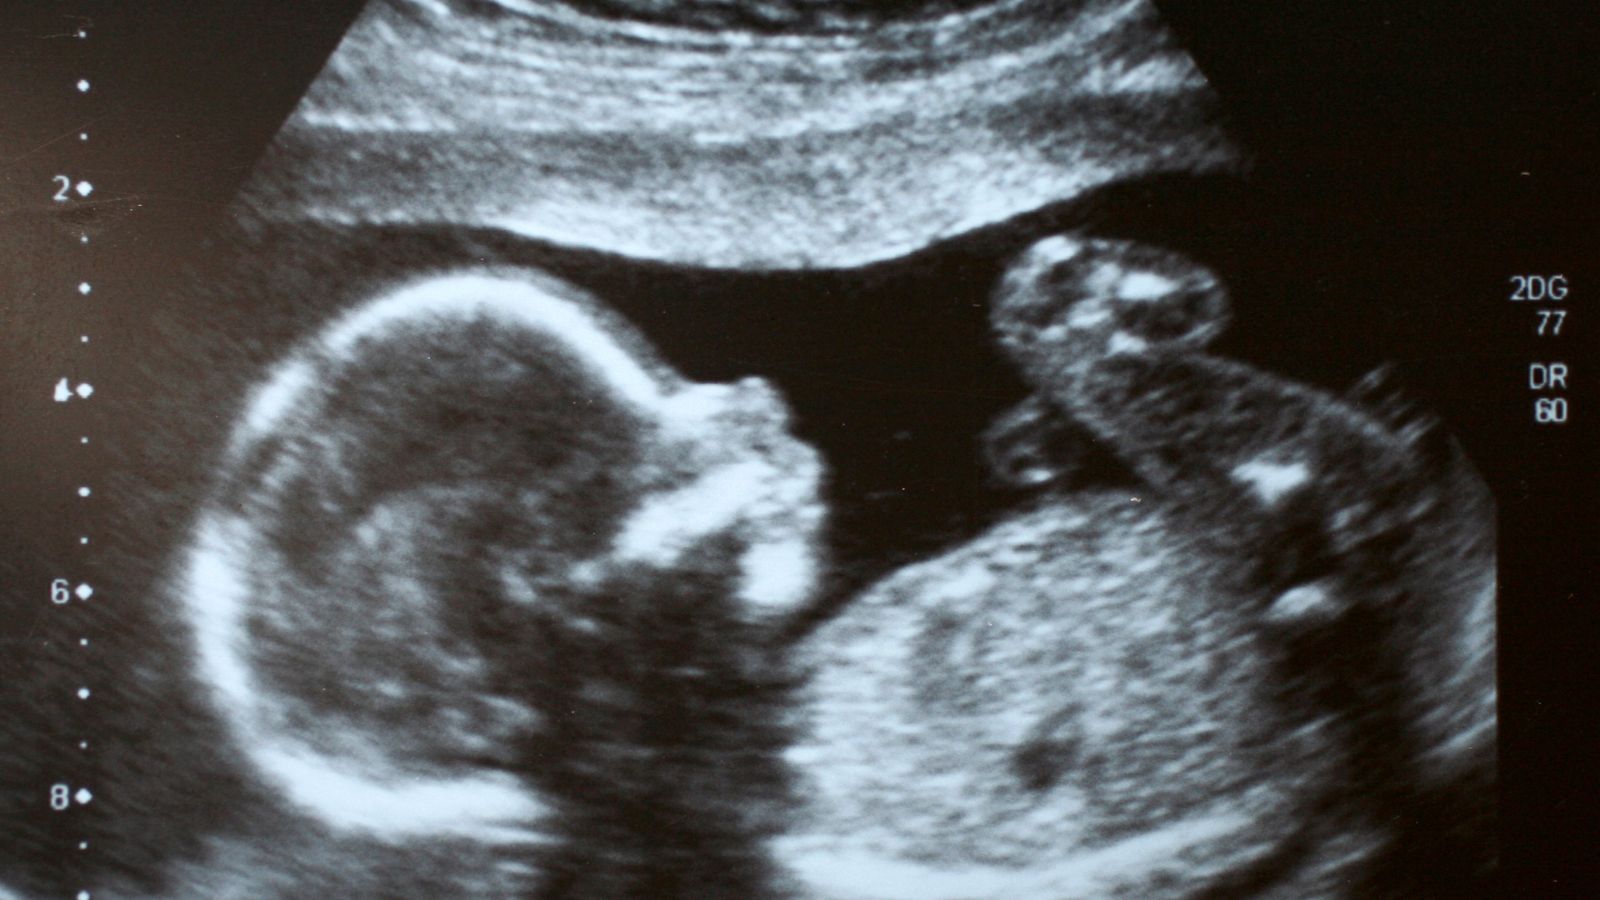

Siêu âm thai định kỳ

Siêu âm là phương pháp tốt nhất giúp phát hiện sớm tình trạng giãn quai ruột ở thai nhi. Thông qua siêu âm, bác sĩ có thể xác định mức độ giãn quai ruột và theo dõi sự phát triển của hệ tiêu hóa của thai nhi qua từng giai đoạn. Mẹ bầu nên thực hiện các lần siêu âm thai định kỳ theo chỉ dẫn của bác sĩ để kịp thời phát hiện bất kỳ vấn đề nào.